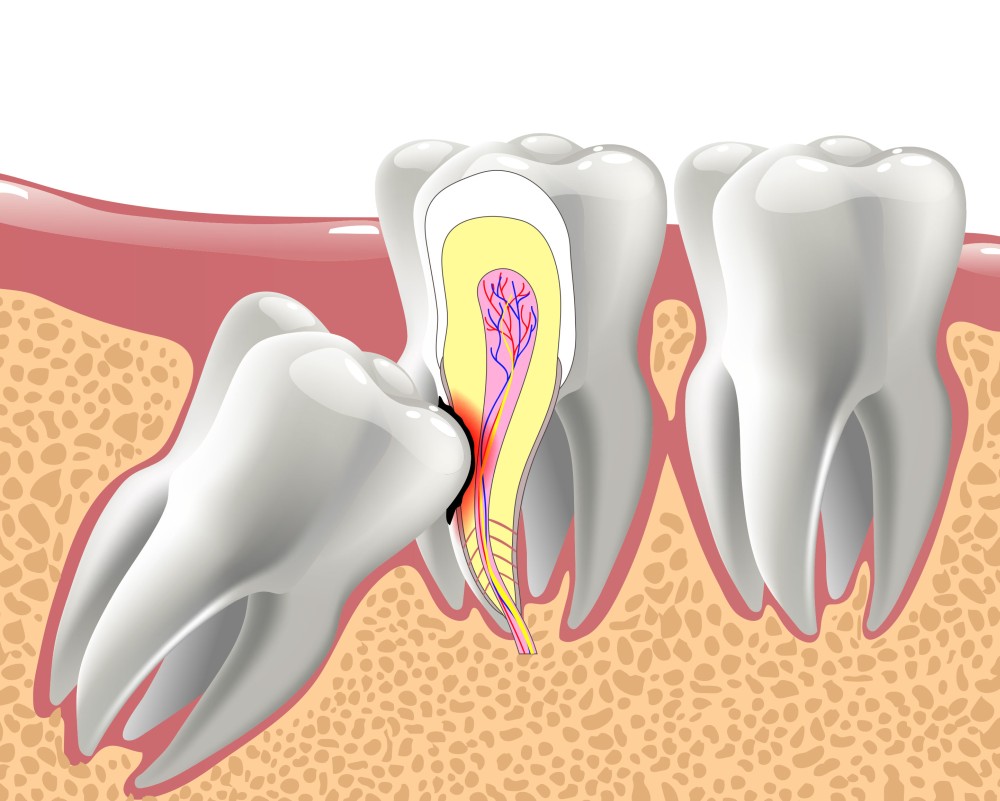

Sometimes though, the way an impacted wisdom tooth is positioned can make it easy for food and bacteria to get trapped around the gum. This can lead to swollen and sore gums (pericoronitis), tooth decay and infection. If you’re having problems such as these, your dentist may recommend taking the impacted tooth out.

If your dentist thinks there’s a high risk of the nerves around your tooth being damaged, you may be offered a coronectomy. This is a procedure where the crown of the tooth is taken out but some of the root is left in place. This may help to reduce the chances of nerves around your tooth being damaged.

Once the anaesthetic has taken effect, your dentist or surgeon will use special tools to gradually ease your tooth out, cutting into the gum if necessary. If your dentist or surgeon has cut into your gum, you may need dissolving stitches to close the wound.